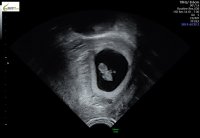

hjertet banket og vi fikk til og med et lite hopp. Målte helt riktig til hvor langt jeg var